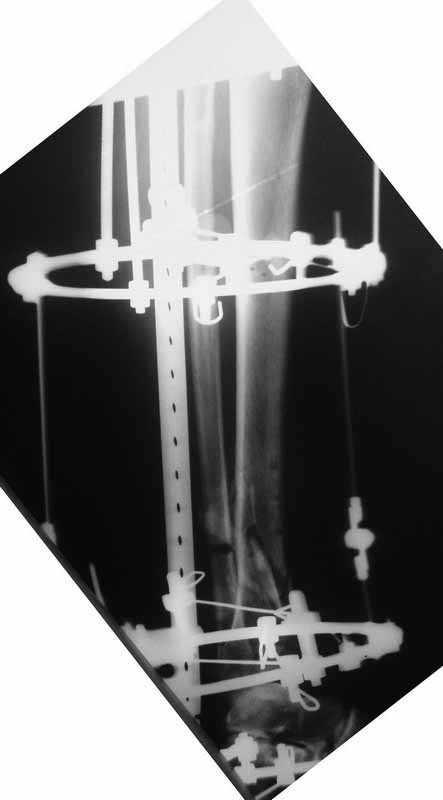

Это гипотрофический ложный сустав. Проблем видится несколько:

1. нарушение трофики в месте перелома.

2. после фиксации в аппарате Илизарова на рентгеногнрамме имеются признаки спицевого остеомиелила. В настоящи момент хотя свищей нет с мая 2011 нет опасно ли фиксировать голень стержнем?

Про восстановление кровообращения. Микрохирургически посадить малоберцовую кость? Есть ли у кого опыт?

На основании каких признаков Вы решили, что кость мертвая! Имеется гиперпластический ложный сустав, как результат недостаточно стабильной фиксации ан предыдущих этапах лечения. В данном случае необходимо решение следующих вопросов:

1 наличие инфекция в зоне ложного сустава

2. коррекция оси

3. окончательная стабильная фиксация

4. исключение предыдущих ошибок

5. оценка своих возможностей.

Открытое вмешательтво на зону ложного сустава, по нашему мнению, не только нецелесообразно, но и вредно! По тактике лечения согласен с Алексеем Семенистым, мы избрали такую- же тактику, но этот вопрос для Вас под номером 5.